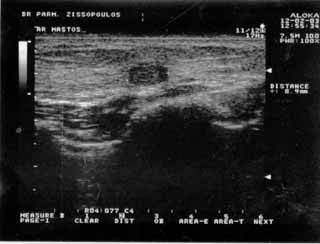

Για την καλλίτερη απόδοση της εξέτασης απαιτείται κεφαλή linear τουλάχιστον 7,5 ΜΗΖ. Ωστόσο και με κεφαλές 3,5 και 5 ΜΗΖ μπορεί κανείς να έχει καλά αποτελέσματα.

Οι απεικονίσεις των περιστατικών που επιδεικνύονται παρακάτω, έγιναν με κυρτές κεφαλές 3,5 και 5 ΜΗΖ, προκειμένου να φανεί, ότι και με τον εξοπλισμό αυτό, που σιγά-σιγά διαθέτουν όλο και περισσότερα ιατρεία, είμαστε σε θέση να έχουμε ικανοποιητικά αποτελέσματα.

Oι τελευταίες 4 απεικονίσεις έγιναν με ειδικό για μαστό ηχοβολέα linear, εναλλασσομένης συχνότητος 7,5-10ΜΗΖ.